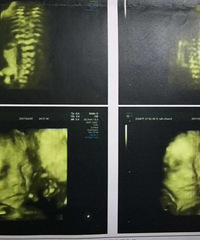

预产期:2017.3.23建卡医院:路北卫生院产检医院:路桥恩泽医院胎宝宝小名:小雨滴生产医院:路桥恩泽医院B超照片/孕期相关照片一张: